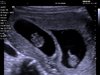

Hej dziewczyny,

w końcu i ja jestem po pierwszym USG.

I mieliśmy niespodziankę życia - BLIŹNIAKI!